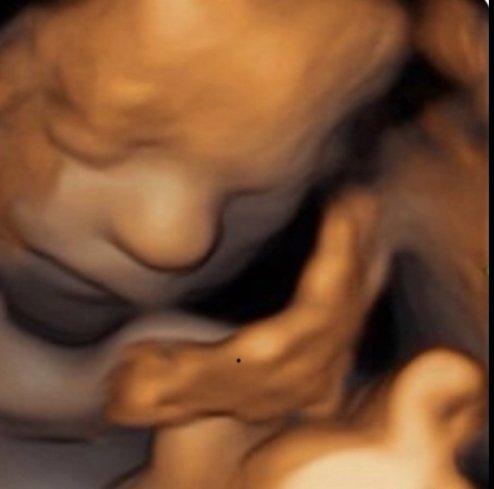

HD Live is an enhanced version of a 3D scan using the latest GE technology available on only the newest machines to render amazingly realistic images of your baby. It uses the most recent generation of beamforming technology combined with speckle reduction algorithms and virtual light sources to create lighting and shadowing effects. This means our sonographer can incorporate light and shadow on baby’s face just as you would see in a person standing next to you.

Our 3D and 4D bonding scans allows you see your baby at an enhanced level of detail, meaning you can see things that cannot be seen in traditional 2D format such as sucking their thumb, smiling, blowing bubbles or opening their eyes.

The perfect time for a 4D bonding scan is between 26-31 weeks because of the optimal balance between baby development and womb conditions but 4D scans can be done anytime from 14 weeks and even as late as 36 weeks we can still get amazing quality images.

The GE Voluson ultrasound machine we use is a very sophisticated piece of technology, its widely recognised worldwide as for providing the best 4D images and you’ll be amazed by the depth of clarity and detail it shows off. In 4D its possible to see your baby do things like sucking their thumb, opening their eyes, blowing bubbles, smiling etc… perfect to start getting to know your baby before he/she is even here.